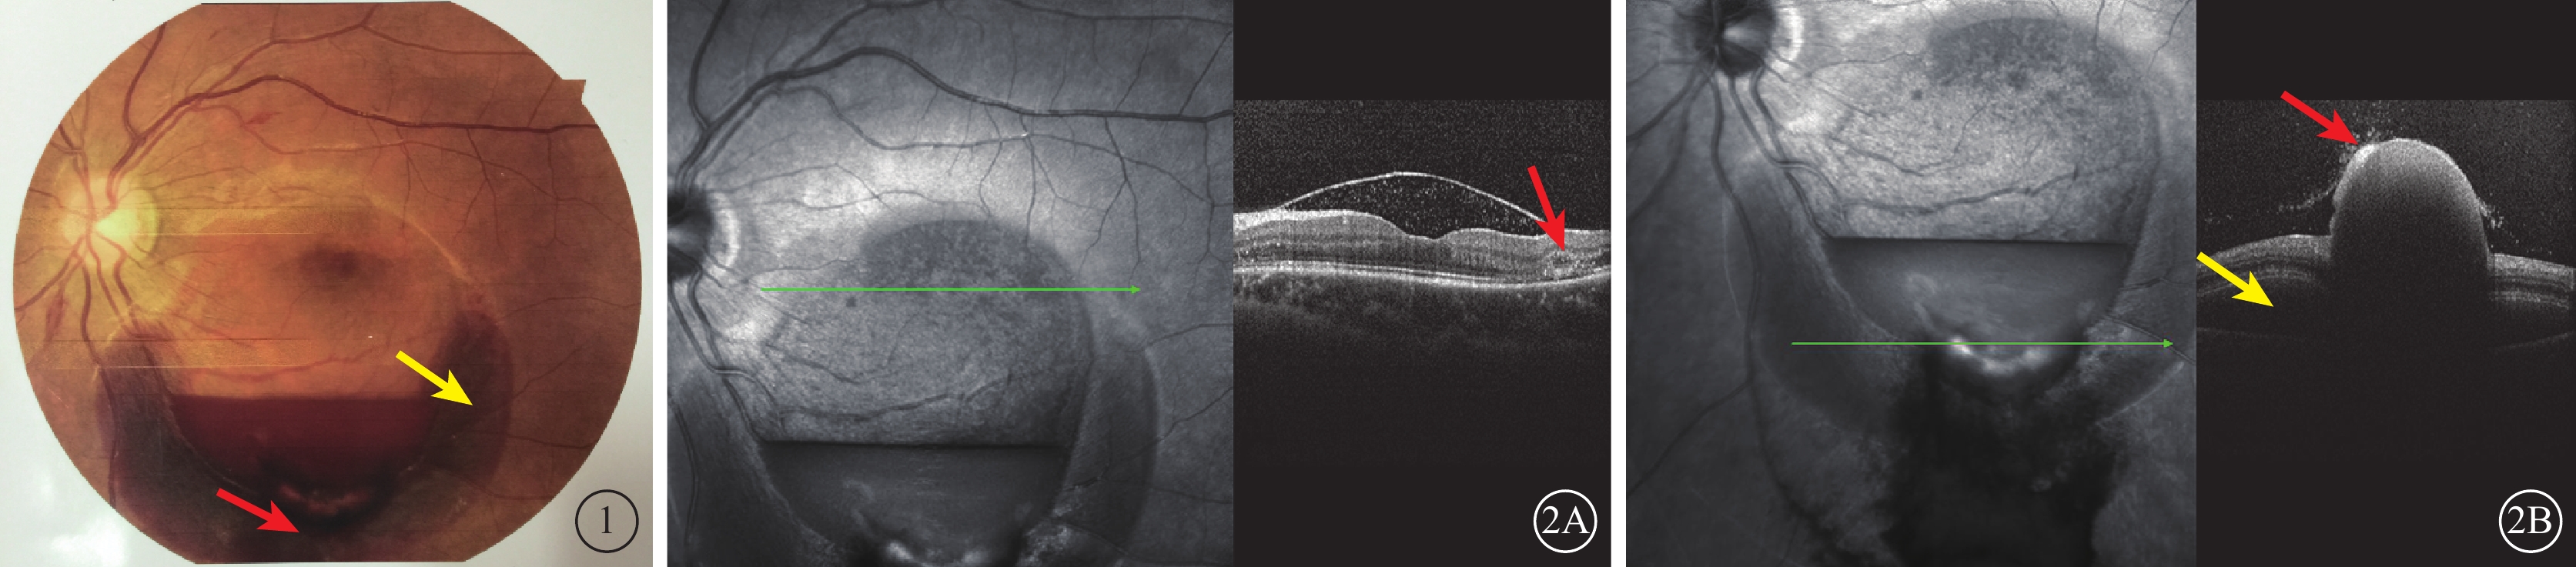

15只眼中,后極部黃斑區視網膜內界膜下出血10只眼。其中,視網膜前1~8個視盤直徑(DD)大小圓頂狀隆起,其邊緣可見視網膜淺層和(或)深層出血7只眼,其中伴少量玻璃體積血3只眼;視網膜前8~10 DD大小圓頂狀隆起,其邊緣可見視網膜淺層或深層出血和后極部視網膜點狀或火焰狀出血3只眼。視盤鼻側視網膜內界膜下出血1只眼,視網膜前1~2 DD大小的圓頂狀隆起,出血區邊緣視網膜淺層或深層出血。黃斑區視網膜深層出血2只眼。視網膜內界膜自行破裂致玻璃體積血2只眼。其中,1只眼為妊娠36周孕婦,因劇烈嘔吐后左眼視力下降2 d就診。黃斑區可見約10 DD大小圓頂狀隆起,下方1/2環狀視網膜下出血,其內可見淡血性視網膜前出血(內界膜下),出血灶1/2處可見液平面(圖1);出血區下方可見玻璃體腔相連的血凝塊,余視網膜平復。OCT檢查,下方環形出血區為視網膜神經上皮層出血,內界膜破裂,出血突出于玻璃體腔,視網膜深層層間出血(圖2)。

圖1

左眼彩色眼底像。視盤邊界清楚,黃斑區約10 DD大小出血區,下方1/2環狀視網膜下出血(黃箭),其內可見淡血性視網膜前出血,出血灶1/2處可見液平面;出血區下方可見與玻璃體腔相連的血凝塊(紅箭) 圖2 左眼OCT像。2A. 出血區液平上方可見內界膜隆起,其下為弱反射信號,內可見點狀中強反射信號;內界膜隆起邊緣可見視網膜深層出血(紅箭)。2B. 下方環形出血區可見出血部位在神經上皮層下出血(黃箭)及內界膜破裂,突出于玻璃體腔的血凝塊(紅箭)

圖1

左眼彩色眼底像。視盤邊界清楚,黃斑區約10 DD大小出血區,下方1/2環狀視網膜下出血(黃箭),其內可見淡血性視網膜前出血,出血灶1/2處可見液平面;出血區下方可見與玻璃體腔相連的血凝塊(紅箭) 圖2 左眼OCT像。2A. 出血區液平上方可見內界膜隆起,其下為弱反射信號,內可見點狀中強反射信號;內界膜隆起邊緣可見視網膜深層出血(紅箭)。2B. 下方環形出血區可見出血部位在神經上皮層下出血(黃箭)及內界膜破裂,突出于玻璃體腔的血凝塊(紅箭)

15只眼中,后極部黃斑區視網膜內界膜下出血10只眼。其中,視網膜前1~8個視盤直徑(DD)大小圓頂狀隆起,其邊緣可見視網膜淺層和(或)深層出血7只眼,其中伴少量玻璃體積血3只眼;視網膜前8~10 DD大小圓頂狀隆起,其邊緣可見視網膜淺層或深層出血和后極部視網膜點狀或火焰狀出血3只眼。視盤鼻側視網膜內界膜下出血1只眼,視網膜前1~2 DD大小的圓頂狀隆起,出血區邊緣視網膜淺層或深層出血。黃斑區視網膜深層出血2只眼。視網膜內界膜自行破裂致玻璃體積血2只眼。其中,1只眼為妊娠36周孕婦,因劇烈嘔吐后左眼視力下降2 d就診。黃斑區可見約10 DD大小圓頂狀隆起,下方1/2環狀視網膜下出血,其內可見淡血性視網膜前出血(內界膜下),出血灶1/2處可見液平面(圖1);出血區下方可見玻璃體腔相連的血凝塊,余視網膜平復。OCT檢查,下方環形出血區為視網膜神經上皮層出血,內界膜破裂,出血突出于玻璃體腔,視網膜深層層間出血(圖2)。

圖1

左眼彩色眼底像。視盤邊界清楚,黃斑區約10 DD大小出血區,下方1/2環狀視網膜下出血(黃箭),其內可見淡血性視網膜前出血,出血灶1/2處可見液平面;出血區下方可見與玻璃體腔相連的血凝塊(紅箭) 圖2 左眼OCT像。2A. 出血區液平上方可見內界膜隆起,其下為弱反射信號,內可見點狀中強反射信號;內界膜隆起邊緣可見視網膜深層出血(紅箭)。2B. 下方環形出血區可見出血部位在神經上皮層下出血(黃箭)及內界膜破裂,突出于玻璃體腔的血凝塊(紅箭)

圖1

左眼彩色眼底像。視盤邊界清楚,黃斑區約10 DD大小出血區,下方1/2環狀視網膜下出血(黃箭),其內可見淡血性視網膜前出血,出血灶1/2處可見液平面;出血區下方可見與玻璃體腔相連的血凝塊(紅箭) 圖2 左眼OCT像。2A. 出血區液平上方可見內界膜隆起,其下為弱反射信號,內可見點狀中強反射信號;內界膜隆起邊緣可見視網膜深層出血(紅箭)。2B. 下方環形出血區可見出血部位在神經上皮層下出血(黃箭)及內界膜破裂,突出于玻璃體腔的血凝塊(紅箭)